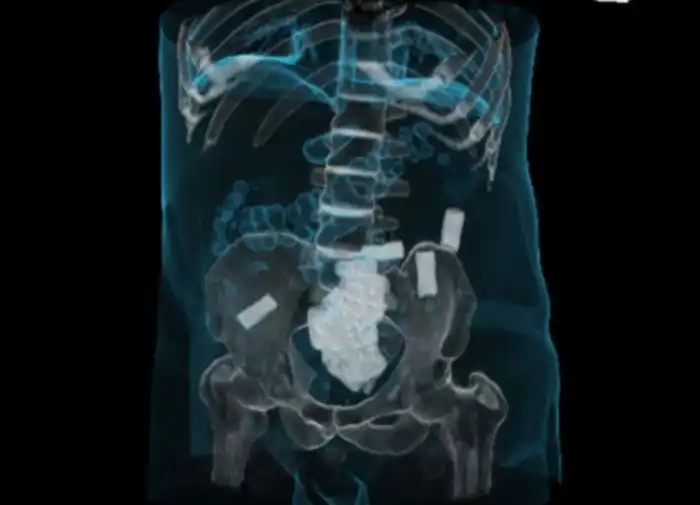

Девять пакетов кокаина

100 пакетиков кокаина в желудке

Наркотики в толстой кишке